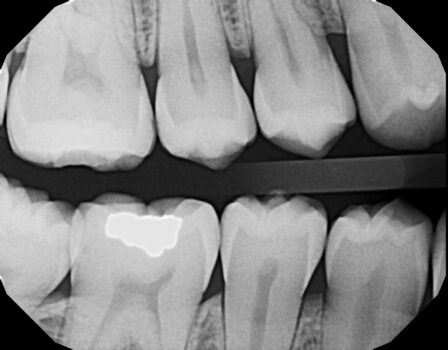

Step into the future of dental care with digital X-rays at Dental Elements, your trusted Downtown Denver dental practice! This innovative technology provides a clearer, faster, and more comfortable way to capture images of your teeth and gums, offering several advantages over traditional film X-rays.